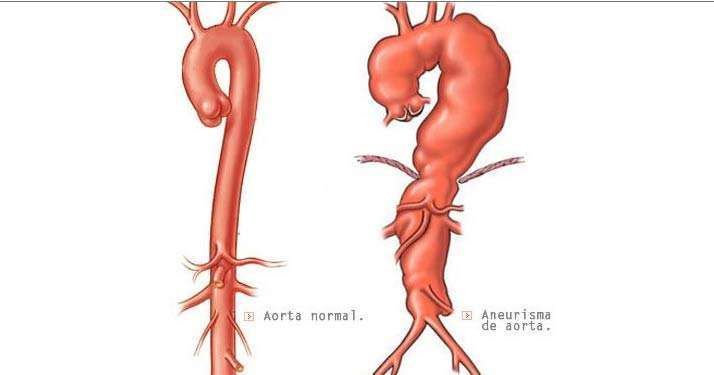

Нормальный диаметр корня аорты: медицинские нормы и отклонения